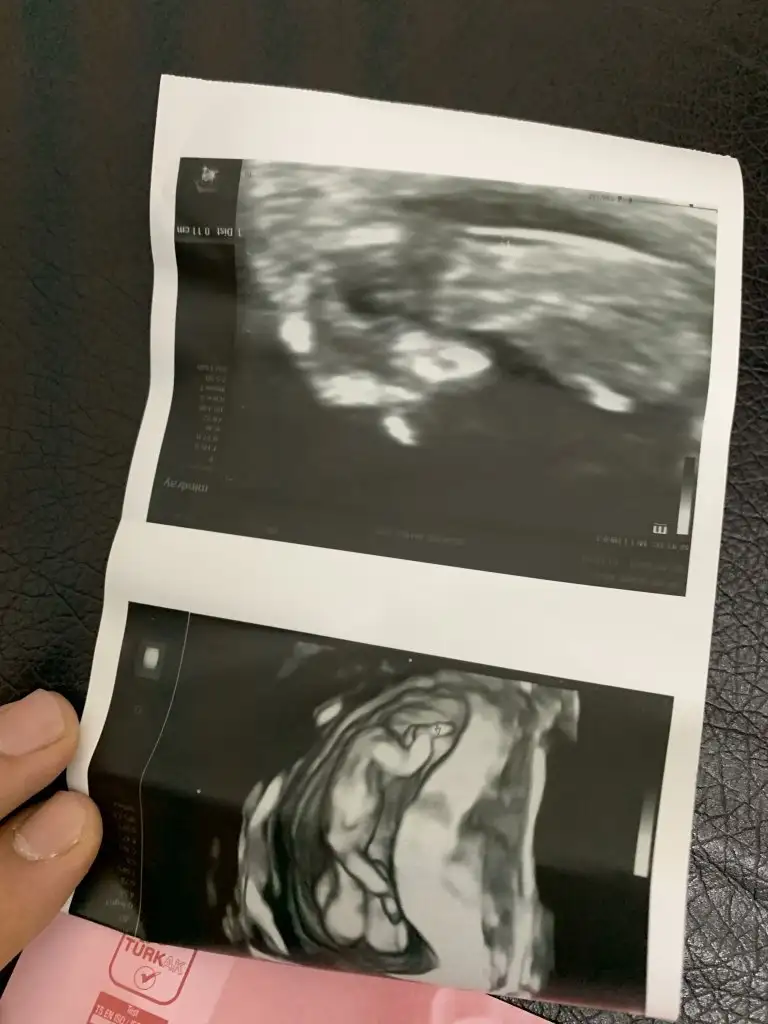

Gecen 12 haftalik istemistiniz bugun cekildik yine :) tahminde bulunabilir misiniz

Son düzenleme: